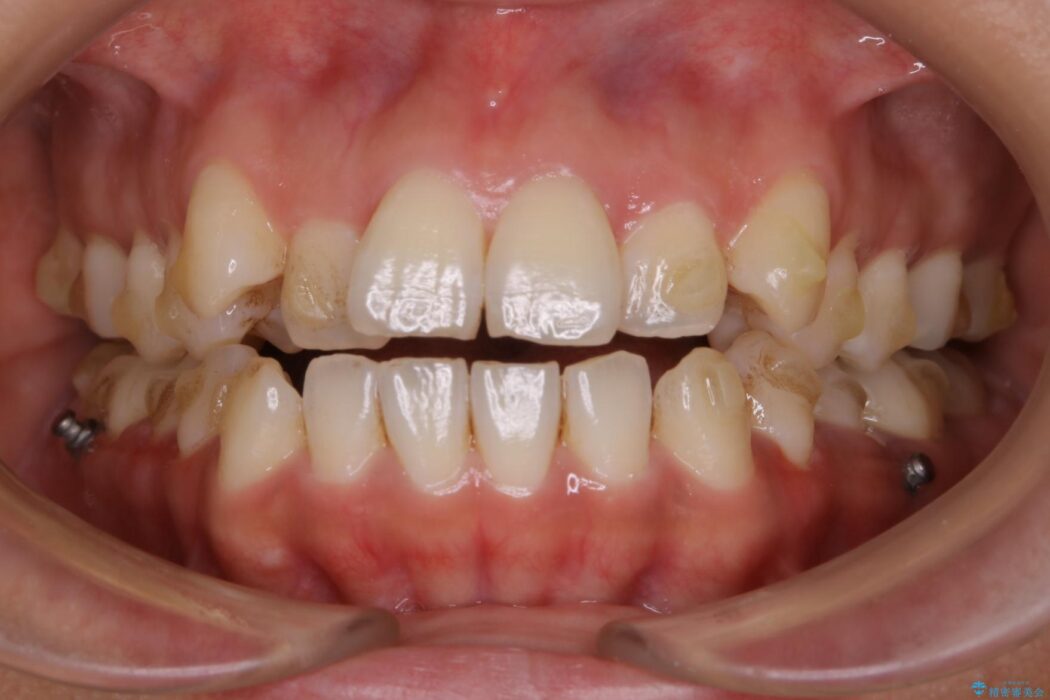

【20代女性】開咬の隙間と歯列の凸凹をまとめて改善する

開咬により上下の噛み合わせが悪く、歯列の凸凹も合わせて治療したいとのことで来院されました。

なるべく非抜歯にて治療をするためインビザライン(マウスピース)とマイクロインプラントを併用した治療を行いました。

きちんと装着時間を守っていただいたこともあり、きれいな歯並びを獲得できました。